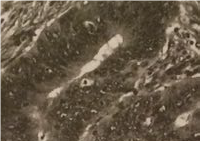

سلول های سرطانی

این اسلاید سلول های سرطانی را نشان می دهد. سلول های سرطانی به صورت توده ای و کاملاً نامنظم هستند. این سلول ها ضمناً با یکدیگر بسیار متفاوتند.